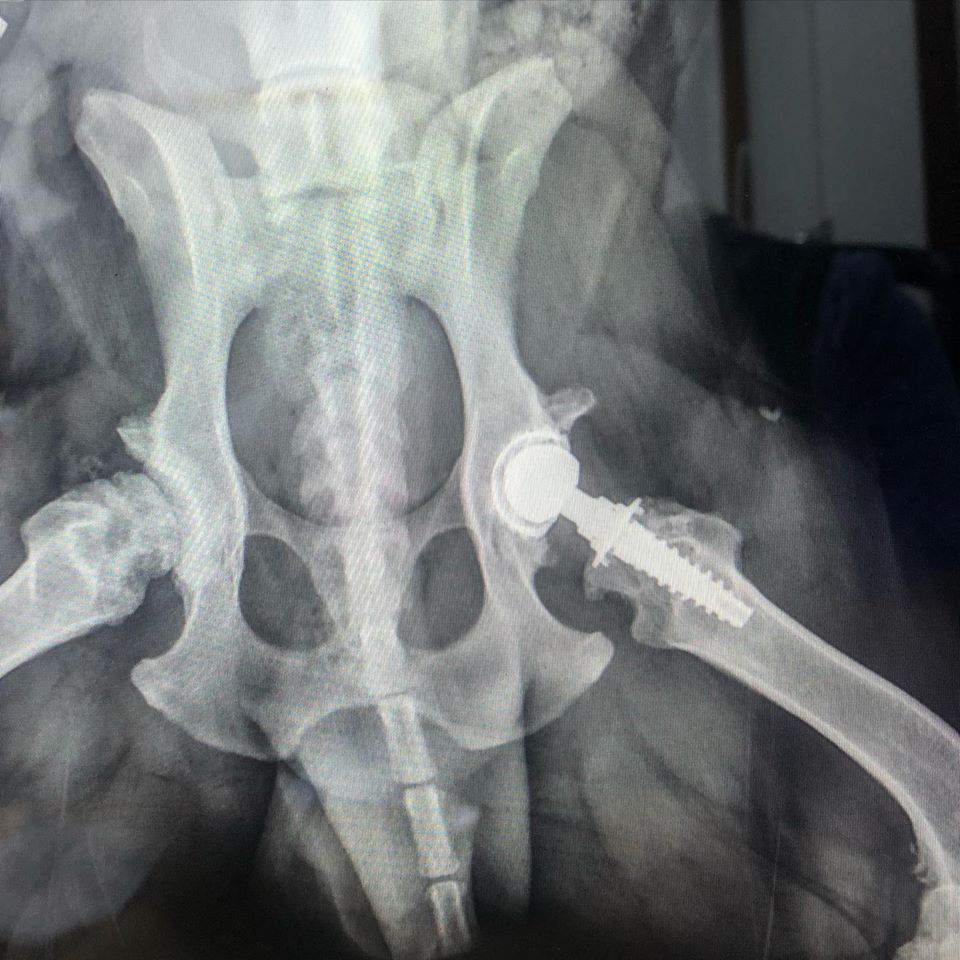

Ponadto zakładamy endoprotezy u psów, które cierpią na dysplazje, zwichnięcie stawów czy złamanie szyi bądź kości udowej.

Założyli mojemu psu endoprotezę. Operacja udana. Psiak znowu cieszy się życiem.